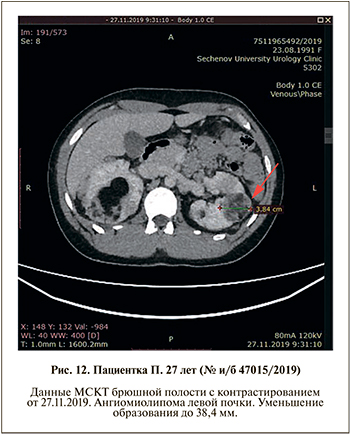

С октября 2019 г. пациентке проводится медикаментозная терапия препаратом эверолимус (Афинитор) 10 мг в сутки. Состояние пациентки удовлетворительное. По данным УЗИ и МСКТ с контрастированием, через 2 мес. в передне-нижнем сегменте правой почки определяется ангиомиолипома максимальным размером 31,3 мм (первоначальный размер образования – 43,5 мм) (рис 7, 8). В верхнем сегменте правой почки визуализируется объемное образование до 64,3 мм (ранее максимальный размер составлял 75,8 мм) (рис. 9, 10). Обращает внимание уменьшение преимущественно мягкотканного компонента. В заднем сегменте левой почки также отмечено уменьшение образования и гематомы: 38,4 по сравнению с 71,6 мм (рис. 11, 12).

По данным проведенного обследования, выявлено уменьшение размеров ангиомиолипом обеих почек на 29,9%. Нежелательных явлений за период проводимой терапии не зарегистрировано.